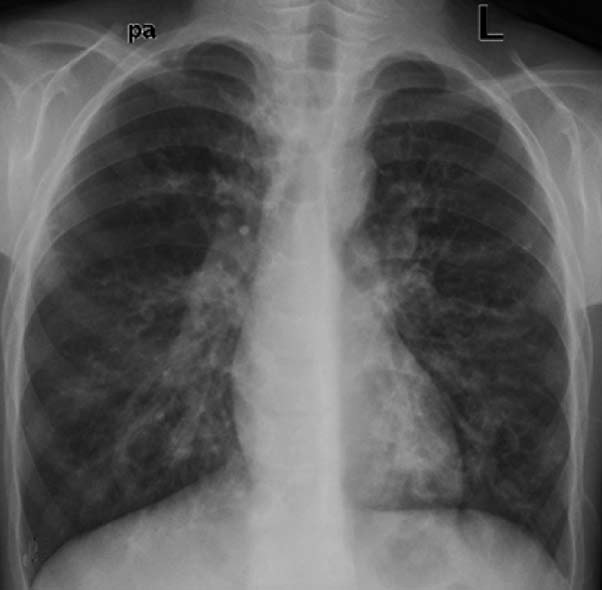

肺特发性含铁血黄素沉着症是罕见的肺部疾患,表现为咯血、贫血和胸片上弥漫实质浸润三联征(triad)【35】。通过在支气管肺泡洗液(broncho-alveolar lavage fluid)、痰或胃汲取液中发现含铁血黄素巨噬细胞(hemosiderin-laden macrophages)得到确诊。继发性含铁血黄素沉着症与全身血管炎、出血性疾病和心脏疾病相关。影像学发现是非特异性和需要与临床和实验室检查结合达到IPH的诊断。胸片显示对称性弥漫或斑片状肺泡阴影很少出现在肺尖,随访过程中这些斑片状可以消失。CT能显示弥漫性或斑片状毛玻璃阴影或有些病例还有间质增厚【36】。